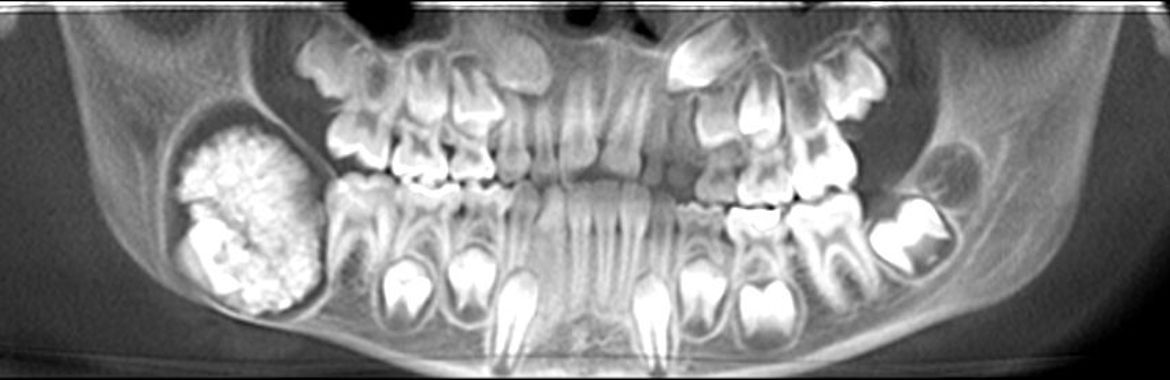

Digitale Volumentomographie

Die digitale Volumentomographie ist ein präzises röntgenologisches 3-D Verfahren zur Darstellung knöcherner Strukturen des gesamten Kopfbereiches. Je nach Fragestellung können auch kleinere Ausschnittsdarstellungen vorgenommen werden. Die Technik gleicht einer konventionellen Übersichtsaufnahme, wobei hier jedoch der Mund geschlossen bleiben kann. Die generierten Aufnahmen gleichen denen eines konventionellen CT, jedoch bedingt die Aufnahmetechnik für zahnärztliche Fragestellungen eine Reihe Vorteile:

- Wahlweise höhere Auflösung

- Geringere Strahlenbelastung

- Weniger Metallartefakte ( Aufnahmequalität mindernde Störungen) durch Zahnfüllungen und prothetische Rekonstruktionen

Ihr Zahnarzt oder Arzt überweist Sie häufig mit einer speziellen Fragestellung wie

- Klärung des Knochenangebots vor einer Implantatversorgung

- Verlauf des Unterkiefernerven vor Weisheitszahnentfernungen

- Lage und Prognose retinierter Zähne (Kieferorthopädie)

- Frakturausschluss

- Zystenausdehnung

- unklare Schwellungen-, Schmerzen

- anatomische Situation der Nasennebenhöhlen (ORL)

Zuweiser: Patienten können direkt über die Homepage zur digitalen Volumentomographie angemeldet werden.